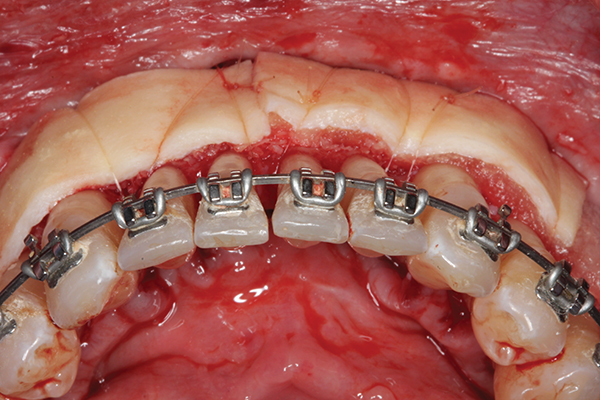

Fig 2. Full-thickness flap reflection. Note

dehiscence and fenestrations throughout. Orthodontic walls are limited to nonexistent.

Figure 2

Fig 3. Corticotomy cuts performed.

Figure 3